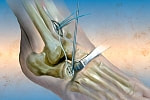

滑膜切除術

滑膜切除術は一般に、関節リウマチがステージ1~2の段階で、まだ軟骨が十分残っている早期に行われる手術です。関節破壊が進んで、軟骨がすでになくなっているようなケースでは行えません。

●内視鏡下の切除術が主流

滑膜切除術は、かつては関節を大きく切り開いて滑脱をとり除く外科的切除術が行われていましたが、現在は内視鏡下での手術が主流になっています。

皮膚に小さな孔をあけ、内視鏡(関節鏡)を挿入して、モニターに映し出された画像を見ながら行う手術です。切開する部分が小さいため、患者さんへの負担も少なく、回復が早いというメリットがあります。

●滑膜切除術のメリット

薬の服用をつづけていても炎症がコントロールできない場合に、炎症を起こしている滑膜そのものをとり除くことで、痛みやはれをやわらげることができます。

●行われる部位

ひざ関節への滑膜切除術は治療効果があり、よく行われます。ただし医師によっては、ひざなど大きな関節には不向きであるとする意見もあります。そのほか、手首、肩、ひじ、足首などに行われます。